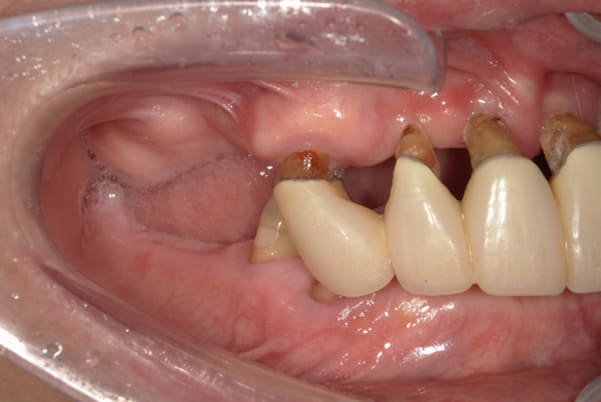

症例レポート[CASE.04]

前歯がとれて痛い、

食事もできず、見た目も悪い

- 性別・年齢

- 女性(60代)

- 主訴

- 前歯がとれて、痛い、食事ができない、見た目が悪く人に会えないので何とかしてほしい

- 治療

-

- 上顎精密金属総入れ歯

- 下顎精密金属部分入れ歯

- 磁性アタッチメント(白金加金) 1歯

- 治療期間

- 約5か月間

- 費用

- 上顎精密金属床総入れ歯:55万円

- 下顎精密金属床部分入れ歯:55万円

- 磁性アタッチメント:11万円×1歯

(白金加金)

合計:121万円(税込)

上前歯はブリッジの差し歯により根が折れ炎症を起こしお痛みのある状態でした。

原因は長期使用により下の義歯の歯が削れたことにより、下前歯が上前歯を突き上げ強い力が加わっていたことが根本的な原因と考えられます。

治療前は、奥歯が下がり、かみ合わせが乱れています。適切な入れ歯はそのままのかみ合わせで義歯を作るのではなく治療後のように、前歯から奥歯までのラインが真っすぐ揃った、かみ合わせの面を適切に付与し、よく咬め、残りの歯に負担がかからないかみ合わせとしました。

とにかく何も食べられないこと、人に会えないことから、なるべく早く何とかしたいとのご希望でした。

患者様とご相談の上、まず早急に上記を回復させるため、初診含め3度の来院でお食事ができ、見た目を回復できるように治療用義歯を作製、装着しました。

本来は、数本の上前歯の折れてしまって残せない歯は抜いてから歯肉の治癒を待ち、数か月後に型どりから作製になりますが、抜歯即時義歯といって、歯を抜く前に型、かみ合わせをとり、抜歯を行ったその日に上下の義歯を装着する特殊な治療法を用いたことで、10日後には治療用義歯をお口に装着することができ、お痛みもなくお食事ができ、ご友人とのお食事にも行けることが可能になりました。

本来、入れ歯作製は技工所と言って、義歯を作製する所に発送するため、作製には時間がかかりますが、院内に技工専用スペースを完備しており、長年、義歯治療において、技工も技術の習得してきましたので技工士さんではなく、かみ合わせの道具も私自身で院内で作製したことで、初診日の次の日にご来院いただきかみ合わせを採ることで、診断、型どり、かみ合わせ、装着まで10日という最短のご希望にこたえらた方です。

ここから、最終的な義歯の作製は従来通り行いました。

抜歯した歯肉が治癒するのを待っている間に、細かなかみ合わせ調整や、審美的なご希望、違和感などをお伺いしそれをもとに、最終義歯を作製しましたが、その作製中も治療用義歯は快適にお使いいただけるため、普段の生活を行いながら通院していただくことが可能となりました。

お写真は治療用の仮の入れですが普段通りお食事ができるとのことで少し食べ物もついています。。。

上顎治療前

上顎治療後

根のみの7本は虫歯にもなっており歯肉は腫れあがっています。

残りの歯もレントゲンで重度の歯周炎によりぐらぐらな状態でした。

下顎治療前

下顎治療後

治療前の入れ歯の奥歯は、治療後の義歯と比較しても分かるように、歯が削れ平らになった状態です。

これにより奥歯のかみ合わせは低くなり、前歯のみが強くあたり、かみ合わせにより上の前歯大きな負担がかかっていたことにより、上の前歯が折れたことが考えられます。